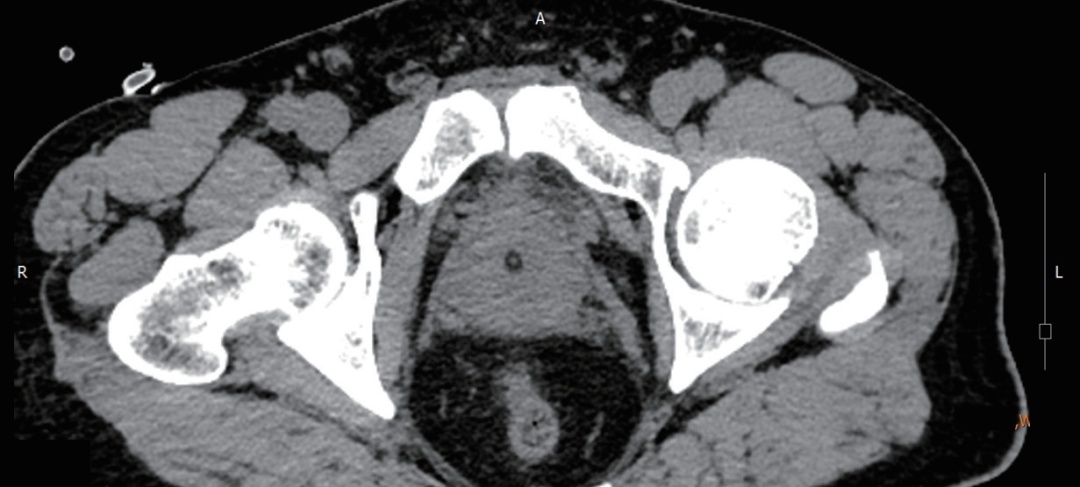

大家都听说过前列腺炎吧?十个男的里就有七八个会有这种情况,足以说明这种疾病的常见性。也正是因为对这种疾病不陌生,所以很多人也提不起关注,即使得了前列腺炎,也不会认为这是一种严重的疾病。我们人体虽然有强大的免疫能力,但是对于前列腺炎来说,是不太可能自愈的,一定要及时地进行治疗。前列腺是人体重要的器官,一旦患上急性前列腺炎,男性会感到痛苦不堪。尤其是急性前列腺炎会导致男性出现尿频、尿急、尿痛、尿不尽等症状,还会影响性功能。急性前列腺炎患者在平时饮食上一定要多加注意,正确饮食有利于病情尽早恢复。 64岁的尹大伯因为高烧来到同济大学附属同济医院进行治疗,看着尹大伯的年纪本以为是什么基础性的疾病,仔细一问才了解原来尹大伯两天前感冒后出现尿频、尿急、尿痛,还伴有下腹部的胀痛不适感,之后又出现了排尿困难的情况。家里人赶紧把尹大伯送当地医院治疗,当地医院也马上给尹大伯做了简单的治疗处理。谁想到今天尹大伯突然发烧到40℃,才有了现在的局面。 看了之前的检查,接诊的罗华荣医师初步判断尹大伯是急性前列腺炎。看着尹大伯痛苦的样子,罗华荣第一时间给他进行了体查,随后又给大伯安排了血常规和尿检以及ct的检查。最后,根据各项全面的检查结果,尹大伯被确诊为急性前列腺炎。